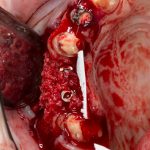

Кстати, обрати внимание на ширину альвеолярного гребня (левая картинка). Она чуть меньше 3 мм. Это объясняет, почему я засомневался в возможности установки имплантатов одновременно с остеопластикой. Понятно и без КЛКТ.

Наперво, мне нужно удалить разрушенный зуб и получить костный аутотрансплантат.

Возвращаемся к основной операционной области. Еще раз посмотрим на альвеолярный гребень, поофигеваем от его ширины и моих грандиозных планов: